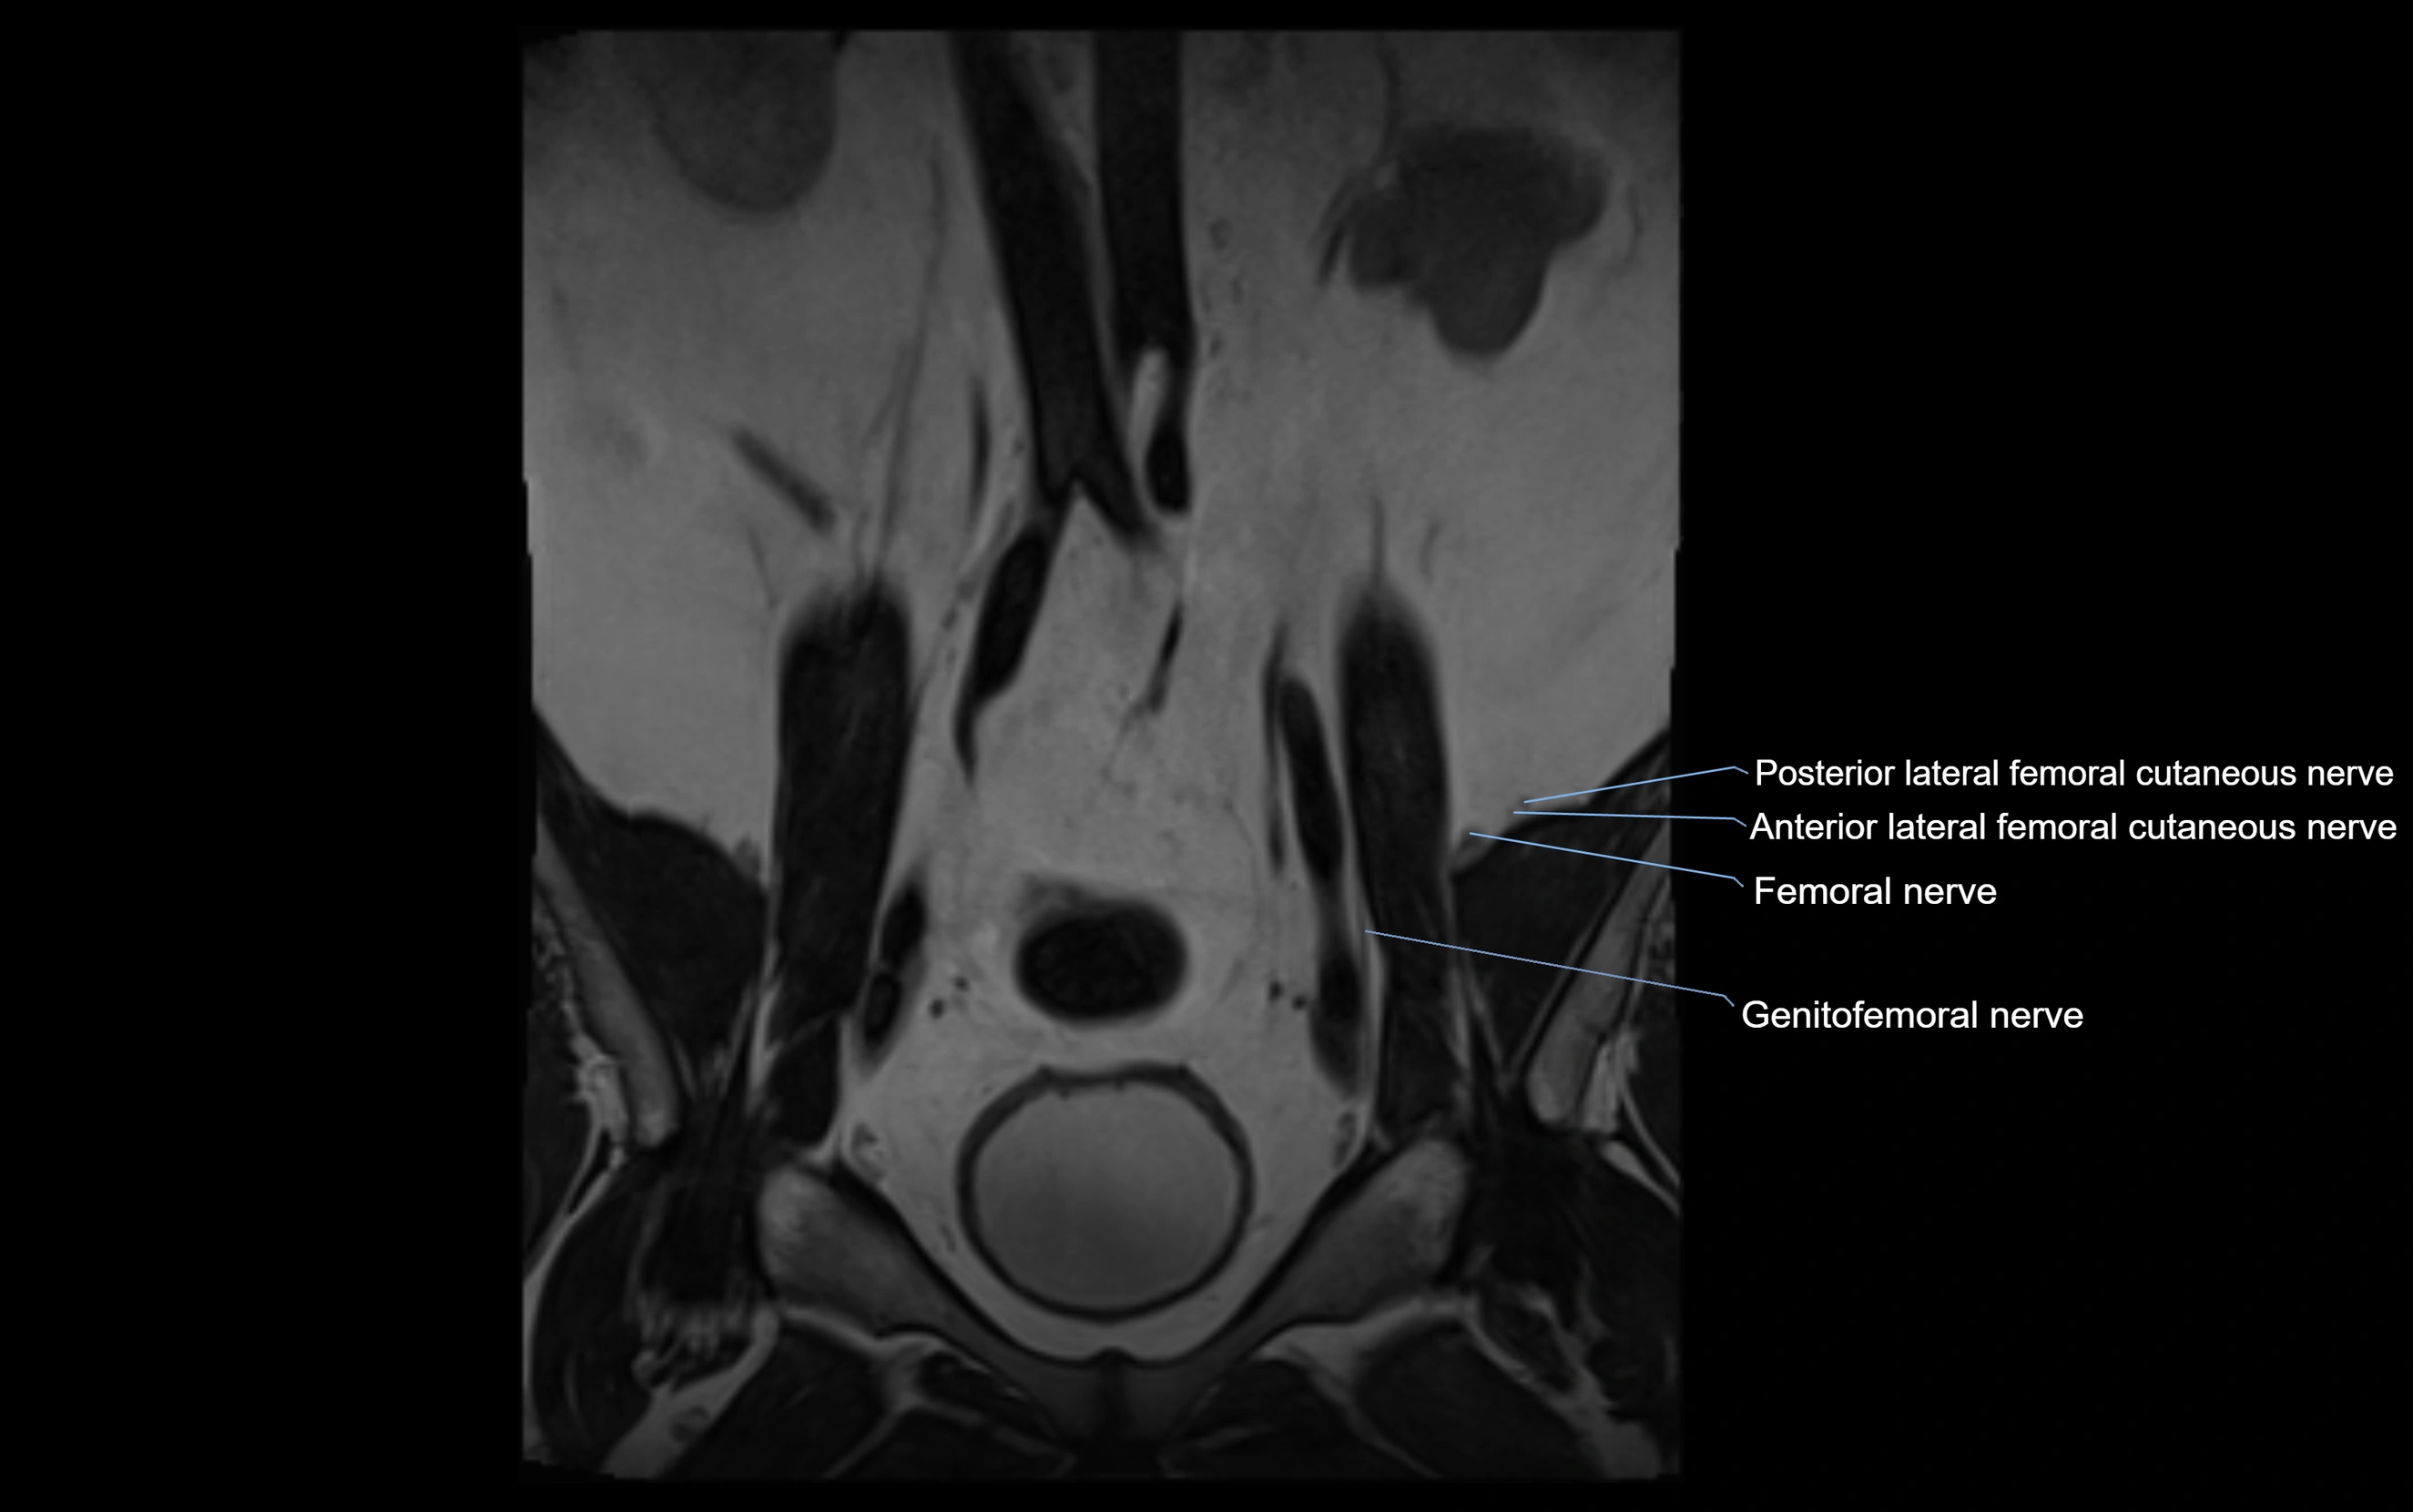

MRI image

image